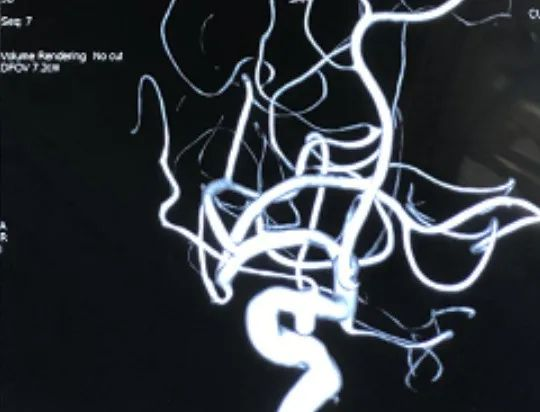

治疗过程:患者多参数监护仪监测下,全麻满意后,常规消毒铺巾,采用改良Seldinger技术穿刺右侧股动脉成功,置入8F动脉鞘。经右侧股动脉鞘,黑泥鳅带领长鞘(Penumbra Neuro MAX6F )到达右侧颈内动脉岩段,撤下泥鳅导丝,微导丝(Synchro 0.014 in*200 cm)带领支架微导管(Prowler Select Plus)达右大脑中动脉M1段,撤出微导丝,再次用微导丝(Synchro 0.014 in*200 cm)带领微导管(Echelon10eV3)超选到达眼动脉段动脉瘤内,退出微导丝。经Echelon10微导管送入(Codman COMPLEX XTRASOFT 3 mm×8 cm)弹簧圈一枚成篮并未解脱,后经支架微导管释放支架一枚(Codman ENTERPRISE 4.5 mm*22 mm)支架打开良好,覆盖瘤颈,撤出支架微导管后解脱首枚弹簧圈,复查造影,弹簧圈位置形态良好,解脱后继续送入(Codman COMPLEXXTRASOFT 2.5 mm×3.5 cm; EV3 3D 1 mm×2 cm;EV3 3D 1.5 mm×4 cm)3枚弹簧圈,期间间断造影确保眼动脉段血流通畅,栓塞后复查脑血管造影,动脉瘤区未见显影,未见造影剂渗漏。手术结束。缝合器缝合右股动脉穿刺点,加压包扎。术后患者麻醉清醒,拔除气管插管,呼唤应答,对答切题,言语清楚,四肢肌力肌张力正常。

动脉瘤大小

术中栓塞:

此患者颈内—眼动脉瘤为宽颈动脉瘤,单纯弹簧圈栓塞有导致弹簧圈脱出或者栓塞不致密复发率高的可能,支架弹簧圈辅助栓塞是目前较为主流的介入治疗方式,Enterprise2支架是自膨式激光雕刻闭环支架,操作简单,精准定位,输送性佳,容易通过迂曲病变。